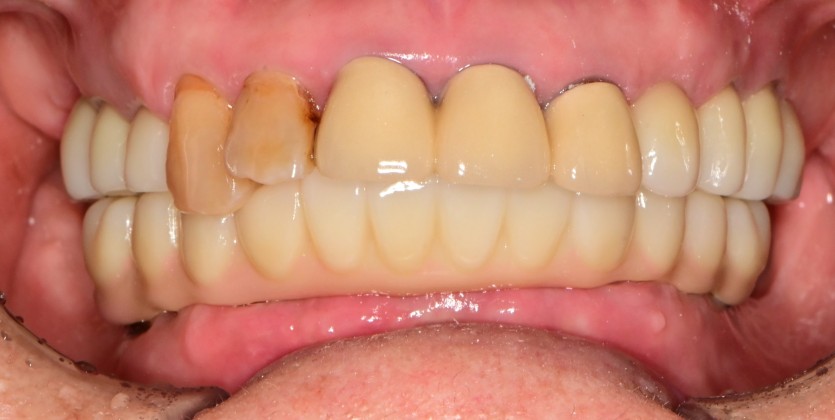

만 82세 하악 풀아치, 상악 임플란트(일부) 증례

하악 풀아치 증례입니다. (상악 구치부 임플란트 포함)

12개의 임플란트로 완성하였습니다.